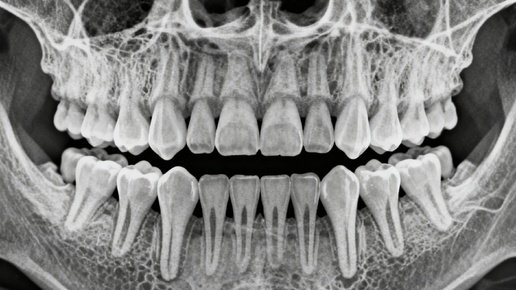

В недрах человеческой челюсти, словно тайные стражи, покоятся зубы мудрости – те самые моляры, что прорезаются в зрелом возрасте, чаще всего между семнадцатью и двадцатью пятью годами. Эти поздние гости, вопреки своему названию, редко приносят мудрость, а скорее – целую вереницу проблем, заставляя стоматологов со всего мира настоятельно рекомендовать их удаление. Но почему же эти зубы, теоретически призванные облегчить пережевывание пищи, так часто становятся источником бед и страданий? Причин тому множество, и каждая из них заслуживает пристального внимания...